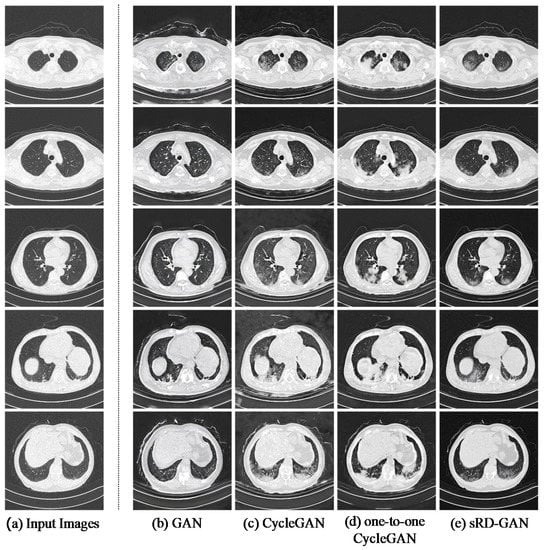

3.3. Qualitative Assessment

3.6. Benchmarking with Existing GANs

- Perceptual realism and quality. While the perceptual quality can be evaluated using the standard FID metric, the actual reality of the synthetic COVID-19 remains challenging due to the domain knowledge requirement. With the help of an experienced radiologist, the Visual Turing Test reveals a promising result achieved by the synthetic images for generating radiography findings of GGO, which is consistent with the real COVID-19 CT images. Furthermore, exhaustive experiments demonstrate the consistent adversary correlation between image diversity and perceptual quality due to the underlying property of the stacked residual dropout, which induces latent space stochasticity and simultaneously encourages a more unconstrained space of image mapping. Thereby, a larger magnitude of stochasticity can generate additional noise artifacts that could be detrimental to the overall perceptual quality and realism of the images. The impact of the adversarial relationship between perceptual quality and image diversity is addressed by a reduced dropout rate at higher dimensional latent spaces. As a result, drastic improvement in the perceptual quality was noticed without affecting the significance of synthetic features generated on the output images. Furthermore, the sRD-GAN also demonstrated superior performance in terms of perceptual quality compared to other GAN baselines, where images generated from the GAN are distorted by a significant amount of noise artifacts. In contrast, the images generated from CycleGAN and one-to-one CycleGAN models failed to effectively eliminate the noise artifacts.